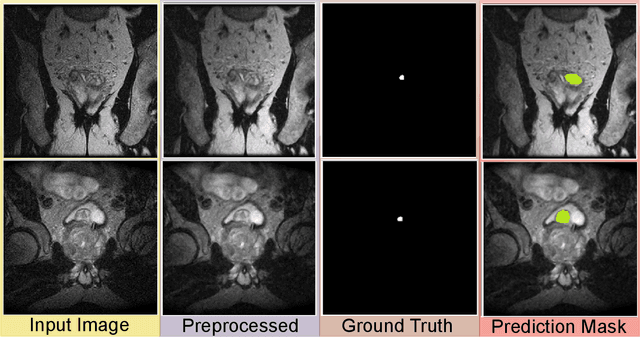

Abstract:Prostate cancer (PCa) is a severe disease among men globally. It is important to identify PCa early and make a precise diagnosis for effective treatment. For PCa diagnosis, Multi-parametric magnetic resonance imaging (mpMRI) emerged as an invaluable imaging modality that offers a precise anatomical view of the prostate gland and its tissue structure. Deep learning (DL) models can enhance existing clinical systems and improve patient care by locating regions of interest for physicians. Recently, DL techniques have been employed to develop a pipeline for segmenting and classifying different cancer types. These studies show that DL can be used to increase diagnostic precision and give objective results without variability. This work uses well-known DL models for the classification and segmentation of mpMRI images to detect PCa. Our implementation involves four pipelines; Semantic DeepSegNet with ResNet50, DeepSegNet with recurrent neural network (RNN), U-Net with RNN, and U-Net with a long short-term memory (LSTM). Each segmentation model is paired with a different classifier to evaluate the performance using different metrics. The results of our experiments show that the pipeline that uses the combination of U-Net and the LSTM model outperforms all other combinations, excelling in both segmentation and classification tasks.